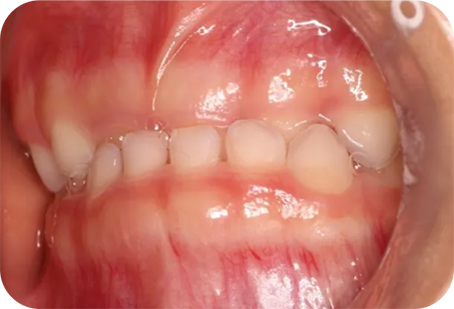

ムーシールドは受け口(反対咬合)を改善する装置です。(受け口とは下の前歯が上の前歯より前に出ている噛み合わせの事です)

主に就寝時に専用マウスピースをつける事で、舌や口腔周囲筋の状態を整え、反対咬合を改善します。

4歳から可能で、特に乳歯列期に治療を行うと、正常な顎骨の成長発育を促すことができるため、正しい永久歯の成長も期待できます。

咬み合わせが逆のまま成長すると、下顎の骨が過成長しやすい状態が続き、結果取り返しのつかないほど大きくなってしまう事もあるため、本人の負担軽減のためにも咬み合わせは早期に治しましょう。

毎晩装置をつけて寝るだけで、こんなに改善するなんて感激しています。子供にも優しく接してくださり、楽しく通院することができました。